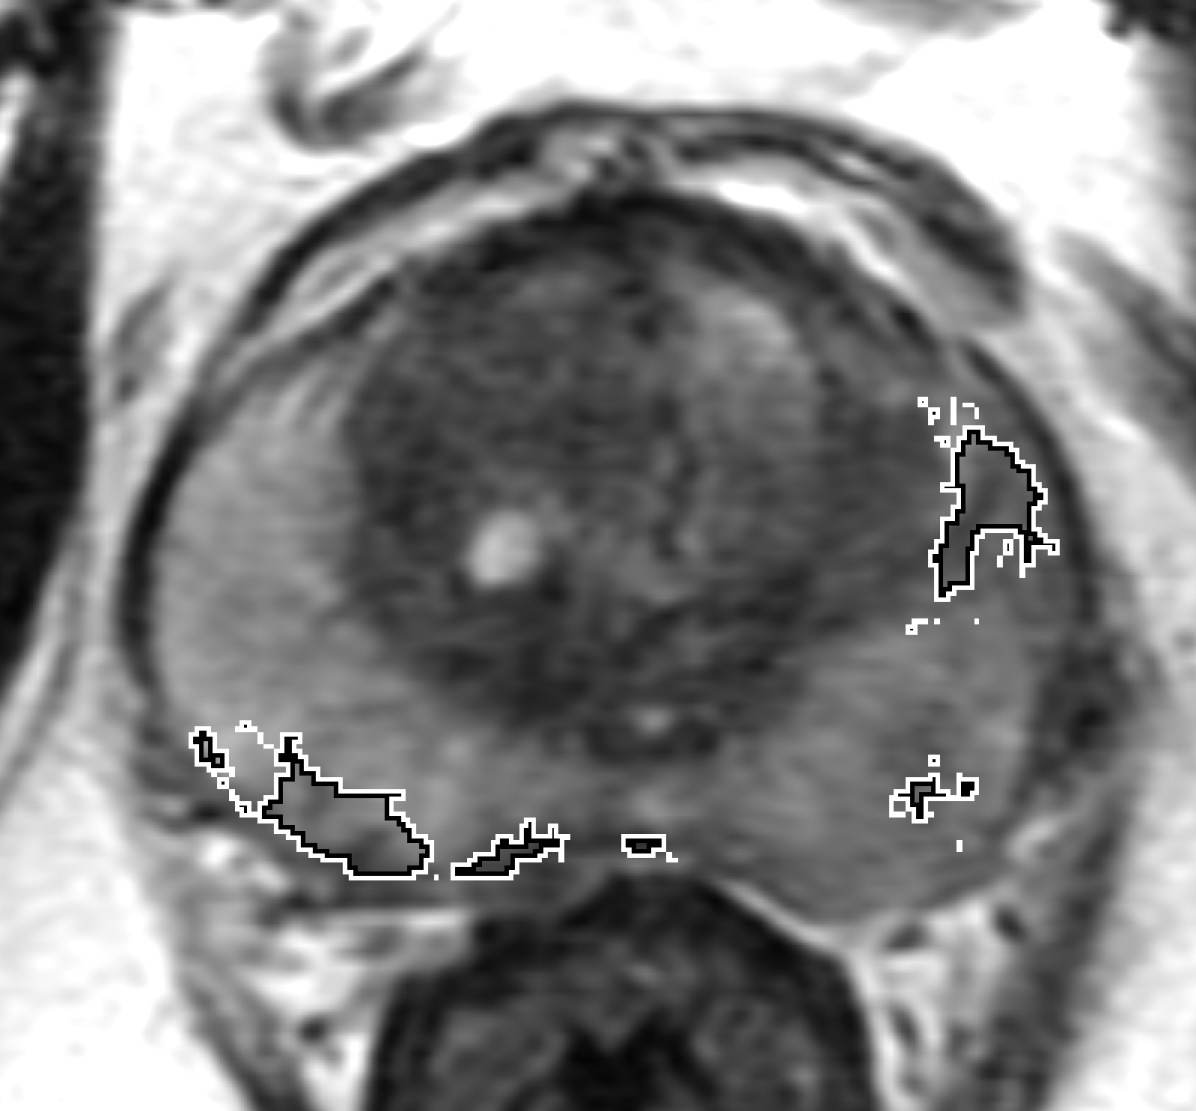

Qualitative Evaluation: Figure 4 shows the same slice as in Figure 2 with aligned T2W, ADC, and histopathology images, and prediction results using current state-of-the-art method [4], our CorrSigNet() and CorrSigNet(T2W, ADC, ) models. It may be noted that [4] fails to detect the cancerous regions on the left and right of the images, while the CorrNet representations alone can identify the cancer regions, and when combined with T2W and ADC images, they predict the cancer regions with high probability. It may also be noted that CorrSigNet(T2W, ADC, ) shows fewer false positives than [4]. This example shows the strength of learning correlated MRI signatures in identifying subtle, and sometimes MRI-invisible cancers. Figure 5 shows more example slices from different patients, comparing the state-of-the-art approach [4] and our prediction results with CorrSigNet(T2W, ADC, ). We note that our model with correlated features (1) can identify subtle and smaller cancer regions, (2) have better overlap with ground truth cancer labels, and (3) have fewer false positives.